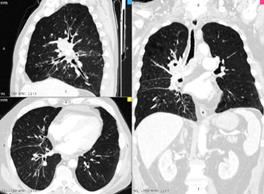

Комп'ютерна томографія (мал.5 А) (мал.5 Б) дослідження на спеціальному комп’ютерному томографі, який складається із здатного до переміщення рентгенівського випромінювача, комп՚ютера і регістратора. Дослідження поперечних зрізів органа за допомогою вузького рентгенівського пучка за кругового руху рентгенівської трубки; інформація про щільність різних органів фіксується спеціальними датчиками, математично обробляється на комп՚ютері і відтворюється на екрані дисплея у вигляді поперечного зрізу людського тіла на різних рівнях; розходження щільності структури органів автоматично оцінюється за допомогою спеціальної шкали, що надає високу точність інформації про будь-яку зону, що цікавить.

мал.10А. КТ

мал.10Б. КТ легень

А

Б

Мал. 5. Компютерна томографія легень

Комп'ютерна томографія є найбільш інформативним методом рентгенодіагностики. Сфера її застосування дуже широка.

Вона дає змогу чітко диференціювати структури тканин і середовищ за щільністю (кров, рідина, пухлина, межі тканин), завдяки чому можна визначити локалізацію і поширення патологічних процесів в органах і тканинах. Інформація надходить на комп’ютер, що перетворює її на зображення у вигляді поперечного зрізу досліджуваного органу. Зображення можна отримати на екрані телемонітора, плівці та полероїдному слайді (рентгенотелебачення).